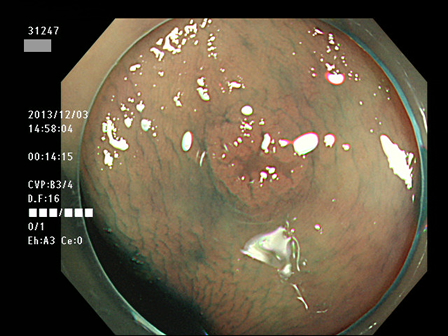

上記100名より抽出した平坦・陥凹型腺腫(=癌化の危険が高いが見落としやすい病変)の内視鏡写真

腺腫発見率 60% (カルテ番号31200〜31299の100名の方の検査結果で集計)

以下のカルテ番号の方に腺腫(Adenoma,Group3〜5)が見つかりました

31241 31242 31243 31244 31245 31247 31248 31250 31251 31254 31255 31256